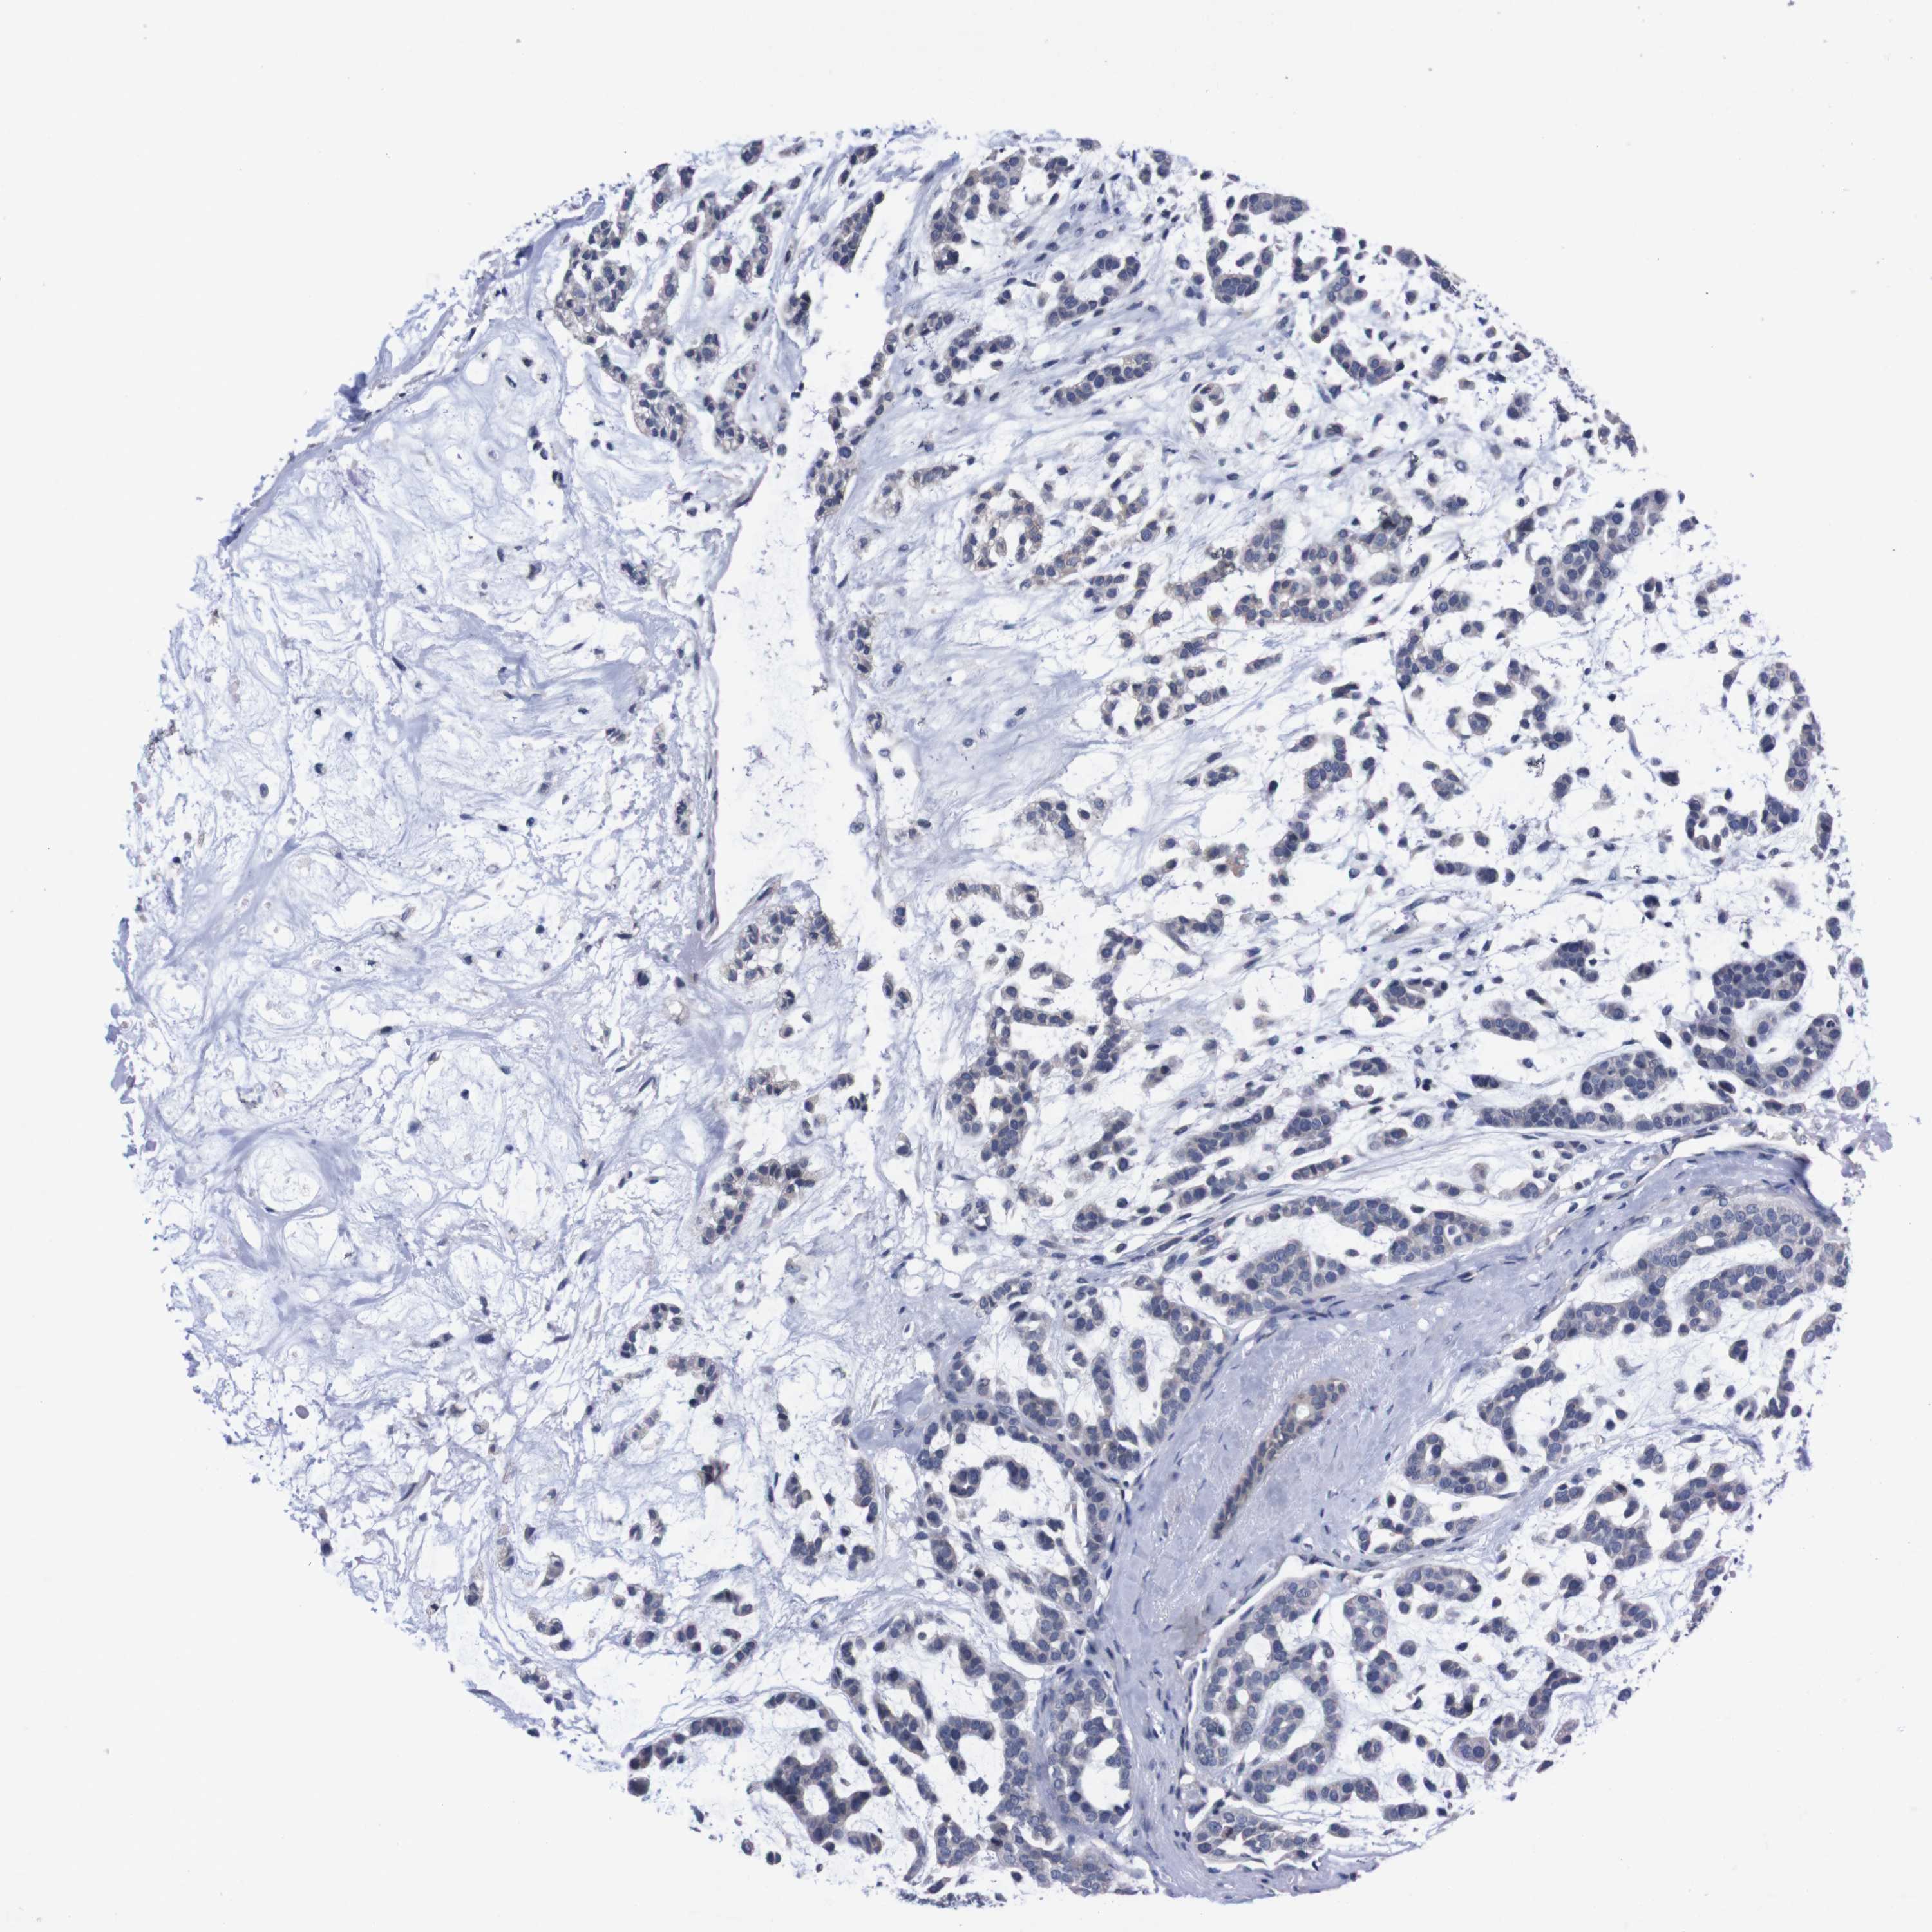

HEAD AND NECK CANCER - Protein expressioni

A mouse-over function shows sample information and annotation data. Click on an image to view it in a full screen mode. Samples can be filtered based on level of antibody staining by selecting one or several of the following categories: high, medium, low and not detected. The assay and annotation is described here.

Antibody stainingi

Antibody staining in the annotated cell types in the current human tissue is reported as not detected, low, medium, or high, based on conventional immunohistochemistry profiling in selected tissues. This score is based on the combination of the staining intensity and fraction of stained cells.

Each image is clickable and will lead to virtual microscopy that enables deeper exploration of all samples and also displays staining intensity scores, fraction scores and subcellular localization as well as patient and tissue information for each sample.

Antibody HPA006746

Staining

High

Medium

Low

Not detected

Intensity

Strong

Moderate

Weak

Negative

Quantity

>75%

75%-25%

<25%

None

Location

Nuclear

Cytoplasmic/membranous

Cytoplasmic/membranous,nuclear

Squamous cell carcinoma, NOS